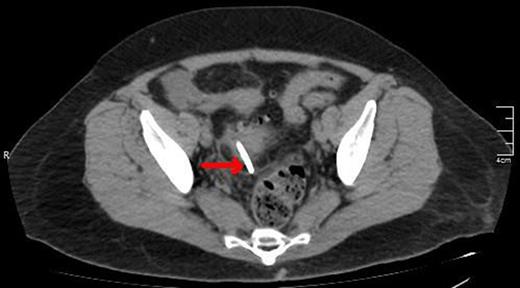

A CT scan showing the upper edge of the biliary stent perforating the antimesenteric surface of the sigmoid colon (red arrow).

A CT view of the same patient showing the lower edge of the biliary stent perforating the sigmoid colon (red arrow).

A lower CT view of the same patient showing the stent (red arrow).